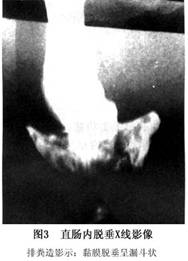

1.发病机制 其机制可能是:直肠下端内的粪便引起便意,在该部分粪便排出的同时,直肠黏膜向下脱垂阻塞肠腔,使近端肠内容物不能进入直肠远端,愈用力阻塞愈明显,便意愈重。但当腹部放松后,黏膜回缩,肠腔开放,近端粪便进入远端直肠,故可再次解出少量粪便。直肠指诊提示直肠腔内黏膜松弛,并且黏膜堆积,手指被黏膜包裹,肠腔变小。排粪造影可见典型的黏膜脱垂呈杯口状的影像。

当患者主诉直肠内有阻塞感、排便不全、便次多,每次粪量少时应考虑患本病的可能,诊断靠下列检查:①直肠指检可发现直肠下端黏膜松弛或肠腔内黏膜堆积。②乙状结肠镜检查虽不能发现内套叠,因插入肠镜时已将套叠复位,但在内套叠处常可见溃疡、糜烂、黏膜红斑或水肿,常易误诊为直肠炎症性疾病。③排便动态造影是有价值的检查方法,可明确本病诊断。典型的表现是直肠侧位片可见黏膜脱垂呈漏斗状影像,部分患者有骶骨直肠分离现象:有人认为,直肠内套叠与会阴下降综合征的症状及临床表现类似。会阴下降时,由于排便时过度摒气,可致直肠前壁黏膜脱垂,因此可能两者是一种疾病。仅在不同发展阶段有不同表现。 医学百科网 | YxBaike.Com

2.排粪造影 是诊断直肠内脱垂的主要方法。其影像特征有:①直肠内黏膜套叠:在排便过程中肛缘上6~8cm处直肠前后壁出现折叠,并逐渐向肛管下降,最后直肠下段变成漏斗状的鞘部(图3),厚约3mm的环形套叠(图4) ;②直肠内全层套叠:环形套叠环的厚度>5mm(图5)。 医学百科网 | YxBaike.Com